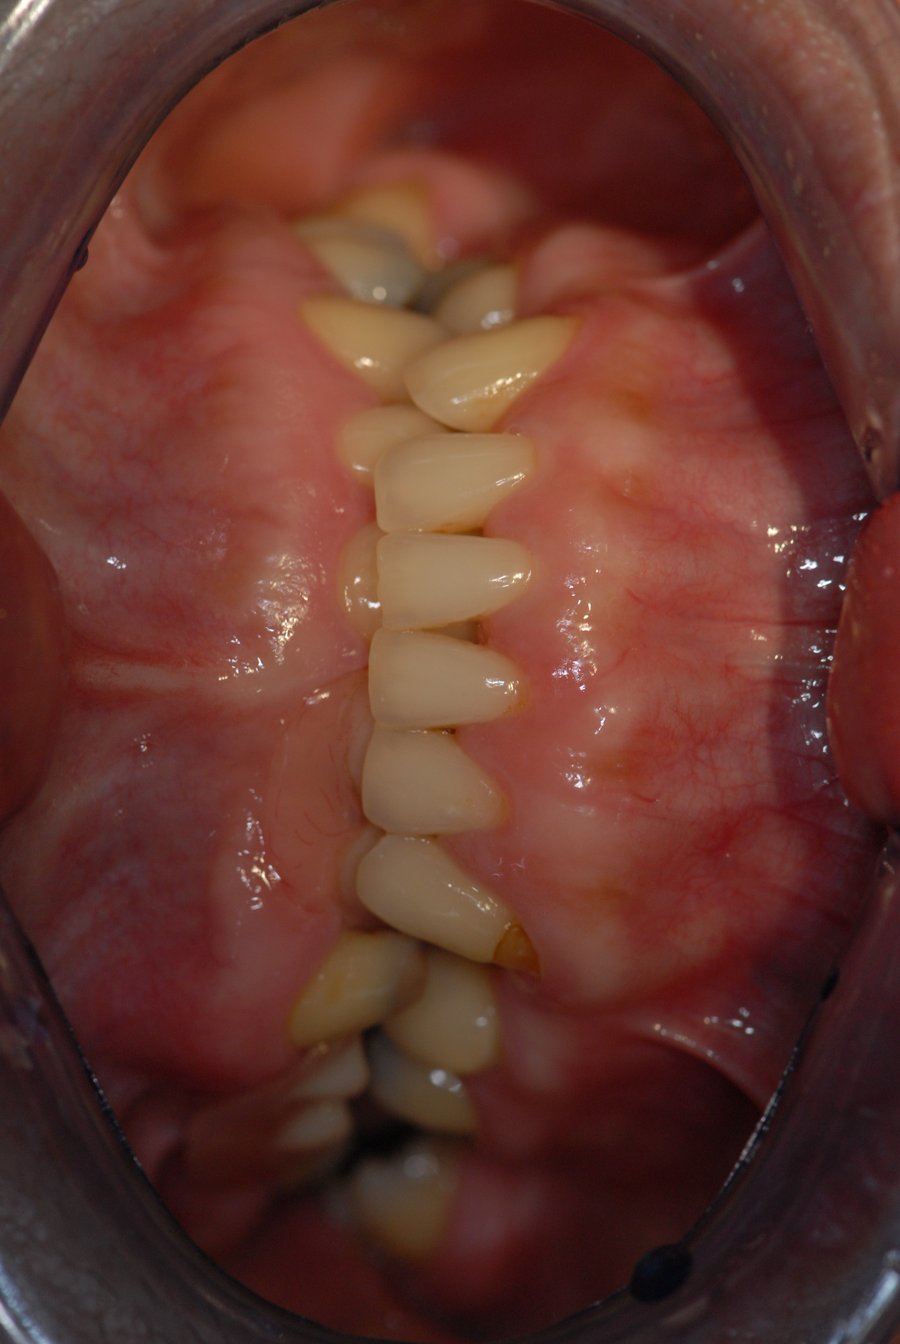

an underbite, a type of teeth misalignment, occurs when the lower teeth protrude beyond the upper front teeth. Cosmetic solutions to malocclusions include: What is a dental implant? Dental implants are designed to replace a missing tooth, and specifically the root of it. Why choose bupa dental care for your implants? restoring missing teeth with dental implants when there is an underbite poses a question of whether to correct the underbite or maintain it. 9 bringing it all together. Alternative treatments to dental implants. It ranges from mild, affecting only teeth, to severe, involving the jaw. ready to learn more about how full mouth dental implants can help resolve your overbite or underbite while also offering.

Dental implants in an underbite patient Dental Implants With Underbite It ranges from mild, affecting only teeth, to severe, involving the jaw. Cosmetic solutions to malocclusions include: restoring missing teeth with dental implants when there is an underbite poses a question of whether to correct the underbite or maintain it. ready to learn more about how full mouth dental implants can help resolve your overbite or underbite while. Dental Implants With Underbite.